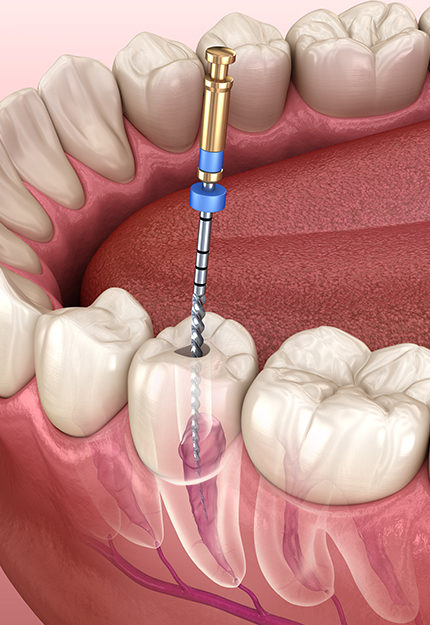

02

다양한 디지털 진단 장비보유

0.1mm 단위까지 오차줄인 진료

성공적인 임플란트 식립을 위해서는 정밀한 진단이 필수적입니다. 3D-CT, 구강 스캐너 등 다양한 디지털 장비를 이용하여 잇몸뼈, 치아, 신경 위치 등을 정확하게 진단해 오차를 최소화하고, 통증 및 출혈을 최소화해 더욱 안전하고 편안한 임플란트 식립이 가능합니다.